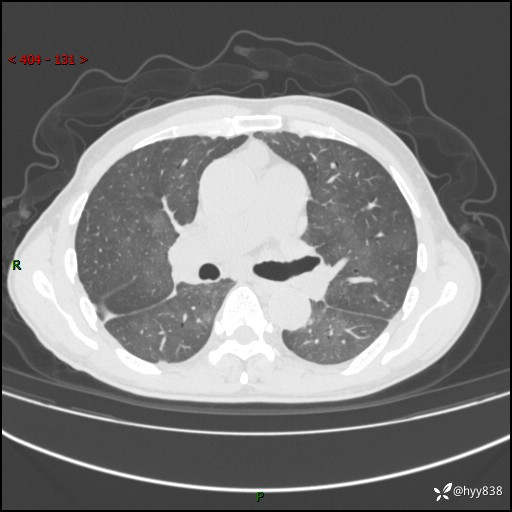

肺结节入院,CT却发现肺部弥漫性病变,what happened---(有结果)

辅助检查:CT

胸部CT平扫

不是讨论肺部结节